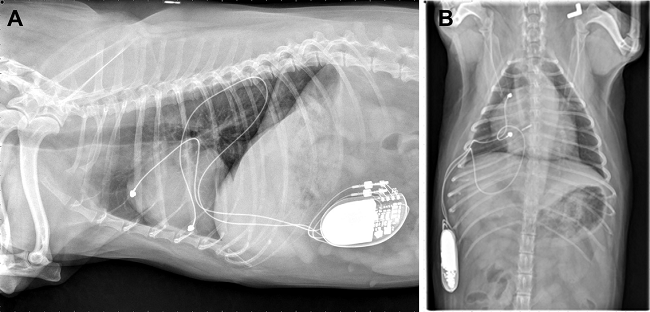

The most effective long-term care for symptomatic second-degree AV block and third-degree AV block cases has been found to be the surgical insertion of an artificial pacemaker (right, above).

(See an x-ray of her at left.) Because of the severely enlarged right chambers, dual chamber pacing

June 2015 article, Colorado State Univ. cardiologists Christian

Weder, Eric Monnet, Marisa Ames, and Janice Bright (right)

reported the case of a seven-year-old female cavalier King Charles

spaniel diagnosed with third-degree atrioventricular (AV) block and both

severe regurgitation through the mitral and tricuspid valves and severe

right atrial and right ventricular dilation and heart failure, and

moderate pulmonary hypertension, all due to degenerative valve diseases.

She had a four-day history of lethargy, exercise intolerance, and

decreased appetite with a very low heart rate of 40 beats-per-minute.

She was treated with a permanent artificial cardiac pacemaker and, due

to the severe structural heart disease and heart failure present, a dual

chamber pacemaker system was recommended in attempt to optimize cardiac

performance by maintaining AV synchrony and heart rate variability.

Because of the severely enlarged right chambers, dual chamber pacing

with epicardial lead placement was recommended. The dog was rechecked at

7 months following implantation, and the owners reported complete

resolution of clinical signs and an increase in the dog’s activity. The

pacemaker required no change in settings.

Permanent dual chamber epicardial pacemaker implantation in two dogs with complete atrioventricular block. Christian Weder, Eric Monnet, Marisa Ames, Janice Bright. J. Vet. Cardiol. June 2015; doi: 10.1016/j.jvc.2014.11.002. Quote: Between November 2013 and December 2013, two dogs with complete atrioventricular (AV) block had a permanent, dual chamber epicardial pacing system implanted. Steroid-eluting unipolar, button-type epicardial leadsa were sutured to the right atrial appendage and right ventricular wall via a right thoracotomy in both dogs. The pacemakers were programmed in VDD mode. Permanent dual chamber epicardial pacemaker implantation was successful in both dogs with no intra-operative complications. One dog had an acute onset of neurologic signs two days post-operatively that resolved within 24 h. Both dogs have had complete resolution of the clinical signs related to the bradyarrhythmia, and one dog has had complete resolution of chylothorax. One dog had a major lead complication characterized by intermittent loss of capture that resolved by increasing the pacemaker output. Based on the outcome of these two cases, implantation of permanent dual chamber epicardial pacing systems is possible in dogs providing an alternative to dual chamber transvenous systems. ... Case 1: A seven-year-old spayed female Cavalier King Charles spaniel was referred to the cardiology service at the Colorado State University Veterinary Teaching Hospital for evaluation of an approximately four-day history of lethargy, exercise intolerance, and decreased appetite with an inappropriate bradycardia (heart rate = 40 bpm). Initial diagnostics included an ECG, echocardiogram, Doppler blood pressure, complete blood count, biochemical profile, thoracic radiography, and urinalysis. Testing for heartworm, Lyme disease, Anaplasma phagocytophilum, Ehrlichia canis, Ehrlichia ewingii and Anaplasma platys was also done. The ECG showed third-degree atrioventricular (AV) block with a ventricular escape rhythm that was unresponsive to atropine (0.04 mg/kg SQ; no AV nodal conduction noted post atropine). The Doppler echocardiogram showed degenerative mitral valve disease (ACVIM stage B2), degenerative tricuspid valve disease with severe tricuspid regurgitation, severe right atrial and right ventricular dilation, and moderate pulmonary hypertension. ... Treatment with a permanent artificial cardiac pacemaker was advised and, due to the severe structural heart disease and heart failure present, a dual chamber pacemaker system was recommended in attempt to optimize cardiac performance by maintaining AV synchrony and intrinsic heart rate variability. Furthermore, the risk of lead dislodgement, intracardiac thrombus, and myocardial perforation were deemed considerable with transvenous pacing due to the severe right ventricular dilation. For these reasons, dual chamber pacing with epicardial lead placement was recommended. ... The dog was rechecked again at 7 months postimplantation and the owners reported complete resolution of clinical signs and an increase in the dog’s activity. Interrogation of the pacemaker at this time showed appropriate atrial and ventricular sensing as well as appropriate pacing and capture. No pacemaker settings were changed. Thoracic radiographs obtained at this visit confirmed correct position of both leads (Fig. 1) [See Figure 1, below].